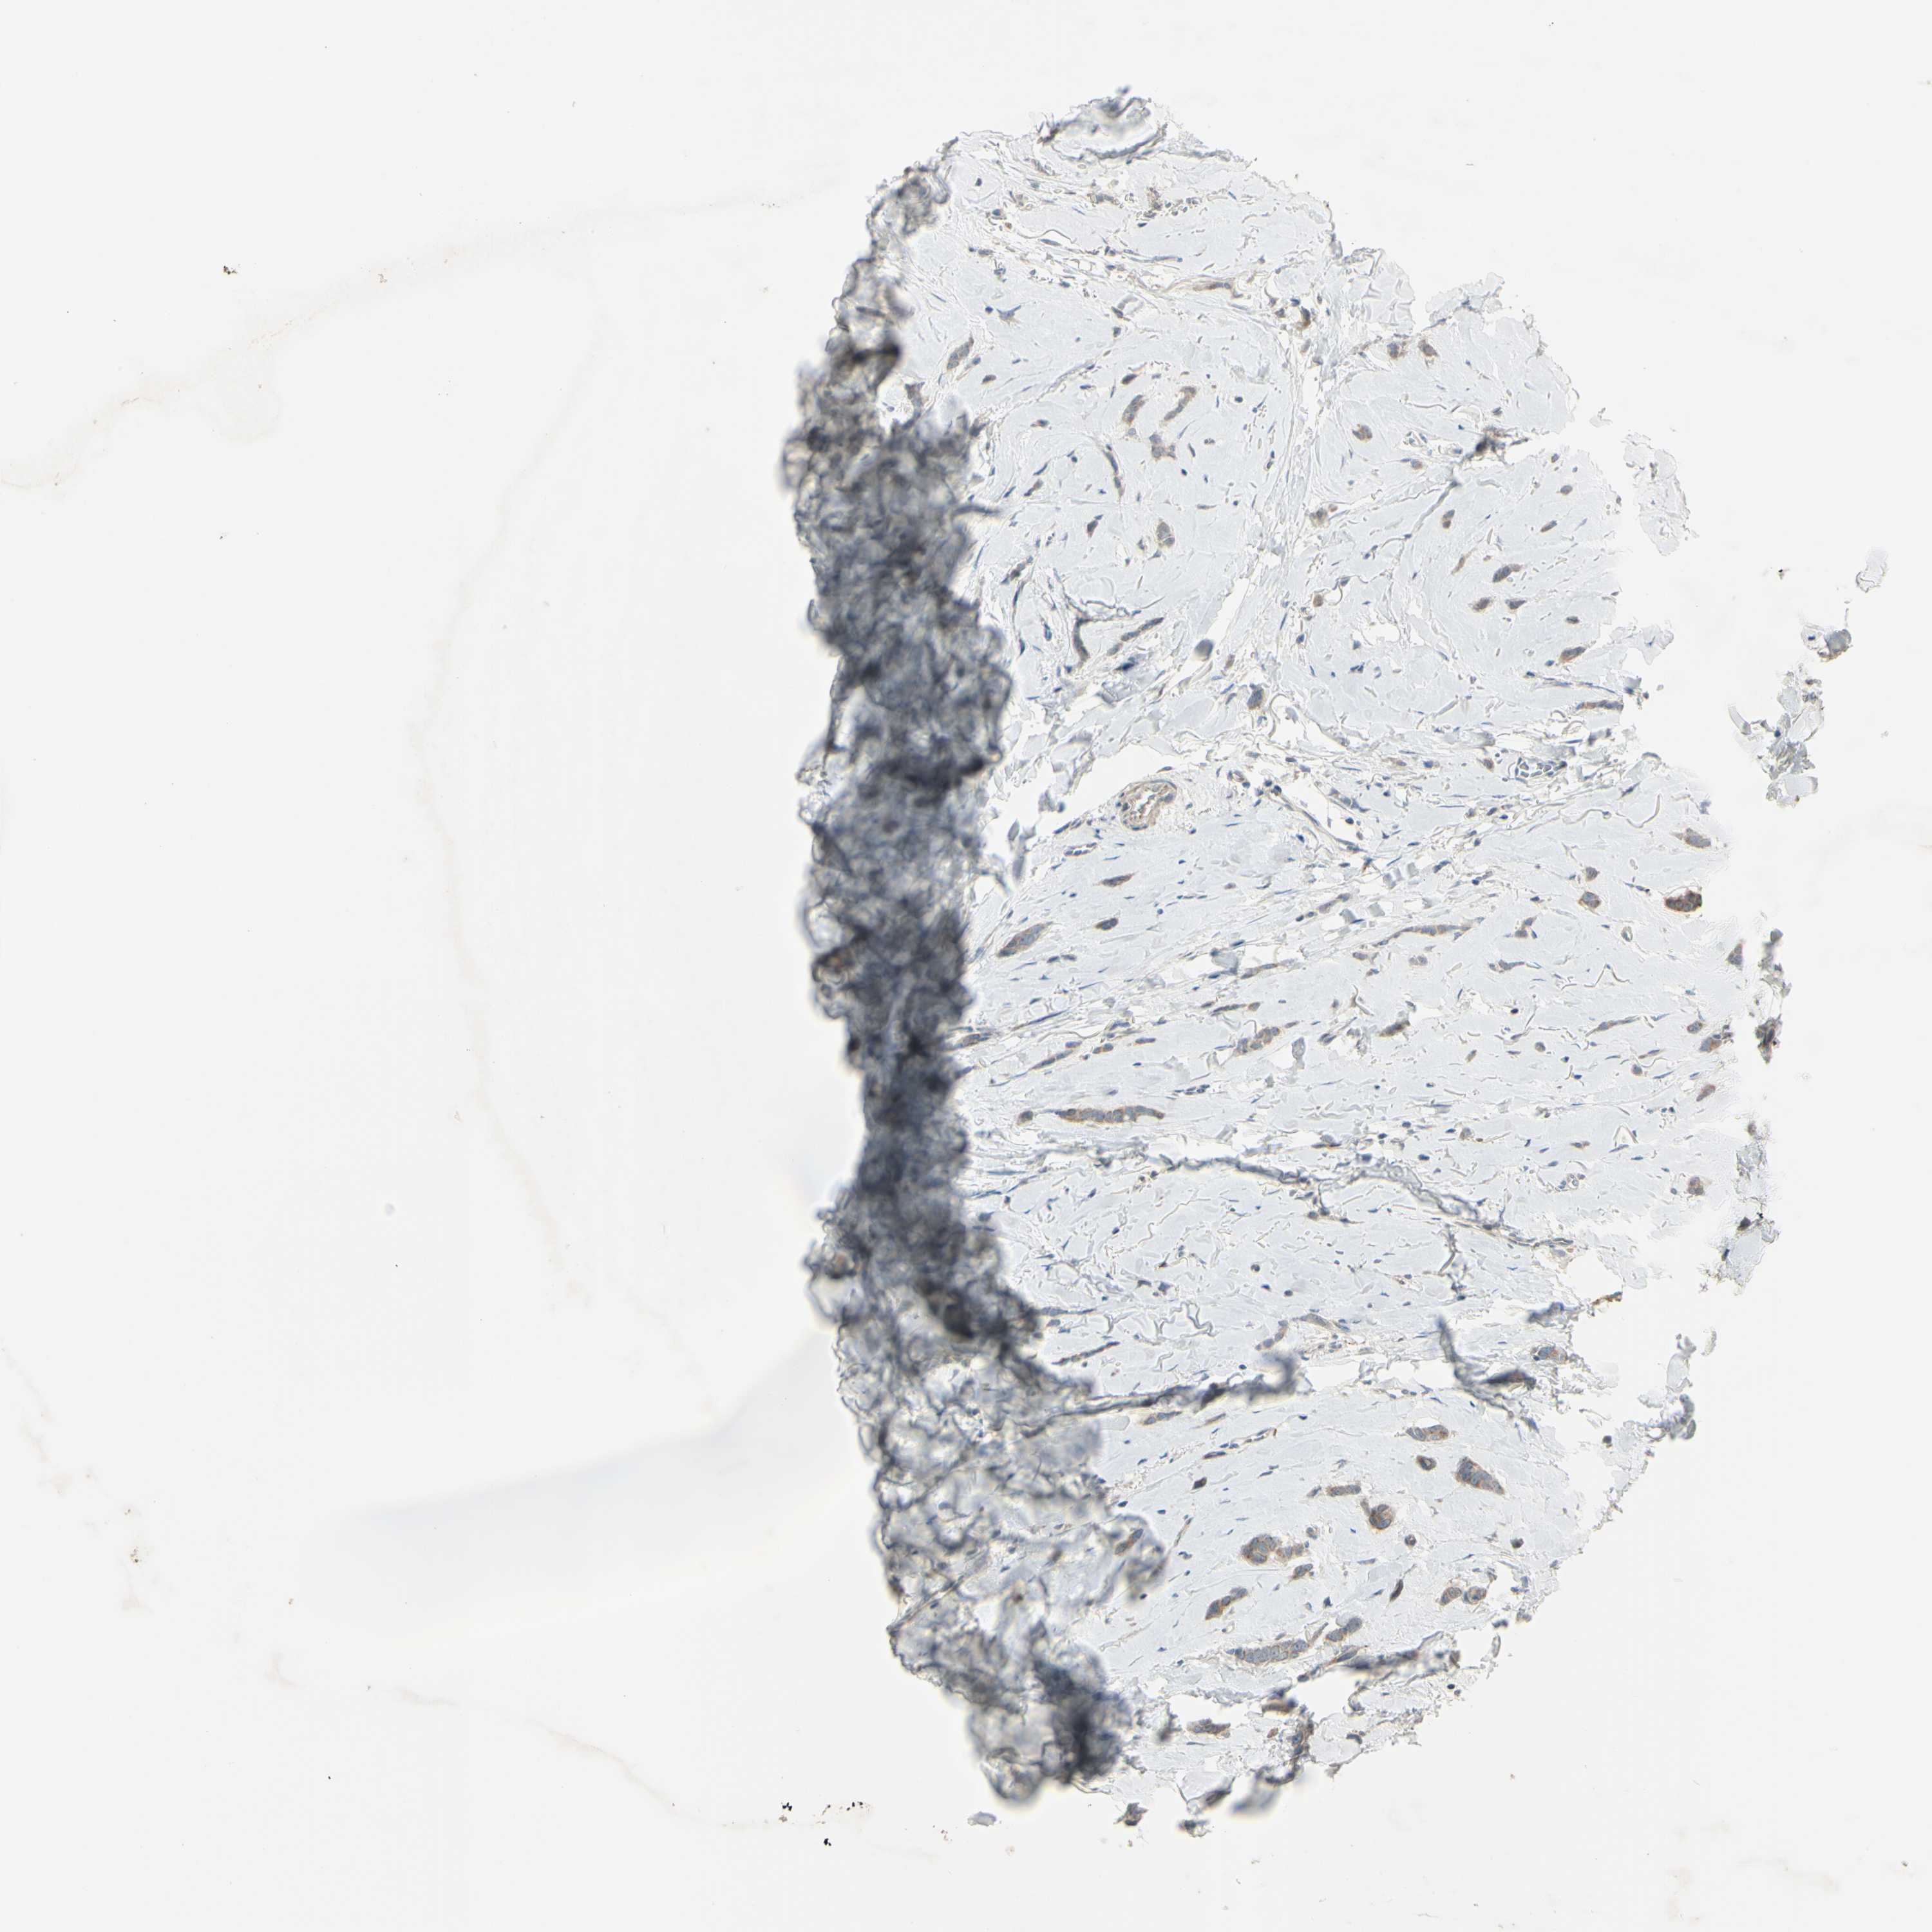

CANCER BREAST CANCER Show tissue menu

Breast cancer

Human cancer